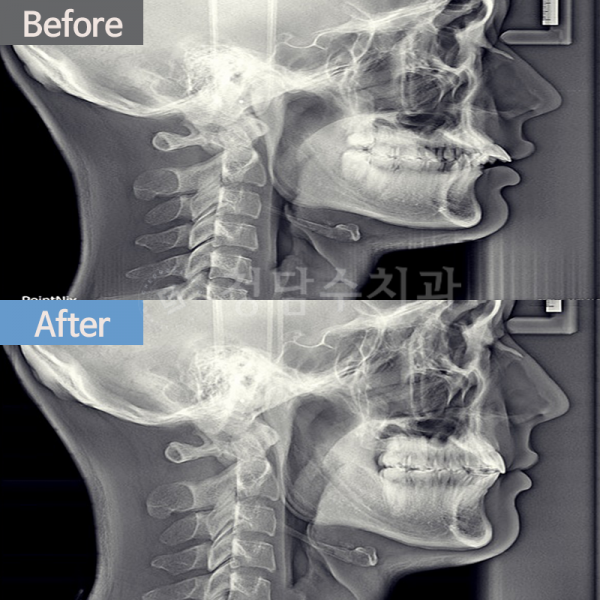

치아교정 돌출교정

돌출교정